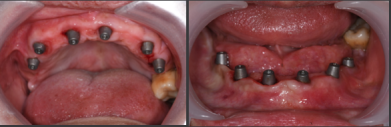

上颌即刻种植即刻修复手术过程

· 上颌360数字化序列导板+预成临时修复体

· 拔除部分牙齿,翻瓣,利用剩余牙齿支持组合导板,辅助基部导板就位固定,基部导板上缘做为去骨线,精确去骨。

· 拔除部分牙齿,翻瓣,利用剩余牙齿支持组合导板,辅助基部导板就位固定,基部导板上缘做为去骨线,精确去骨。

· 全程导板就位,引导种植体植入,安装复合基台。

· 种植体植入位置偏腭侧,唇侧骨量过于丰满,上颌骨前突,去骨修整骨边缘。

· 口内pick-up 固定临时修复体,患者上下颌咬合关系良好。

· 第一幅临时修复体戴入4个月后,种植体周围软组织健康,15.25行种植二期手术。

· 口扫获取种植体周围软组织及咬合关系信息。

· 数字化设计第二幅临时修复体,PMM切削,上下颌各修复12个单位的修复体,16.26单端桥设计

· 第二幅临时修复体戴入口内,修复效果良好,前伸侧方咬合无干扰,预留清洁通道。